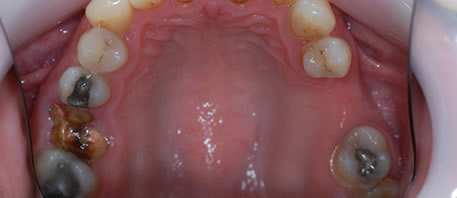

Before Dental Implant

dental implants northern ireland

After Dental Implant